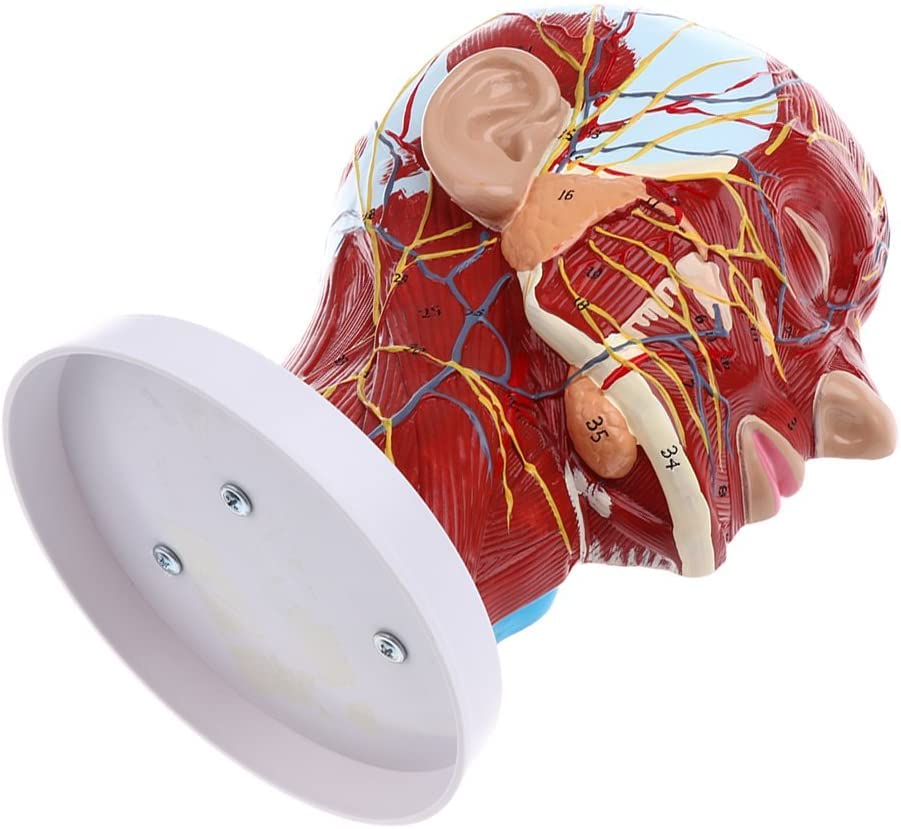

Description:A natural lifesize superficial neurovascular muscle modelMaterial: PVC, PC programmed advanced paintingHighly accurate 3D printing and spatial structureShows details of the human right head and neck and median sagittal plane, including exposed superficial muscles of face, superficial blood vessels, nerves, and parotids of face and scalp, the inner structure of the upper respiratory tract and the sagittal section of cervical spineSuitable for teaching, display, presentation and demonstration in hospital and aesthetic field.Specification:Size: 27 x 21 x 21.5 cm/ 10.6 x 8.3 x 8.5 inchPackage Includes:1 Piece brain model